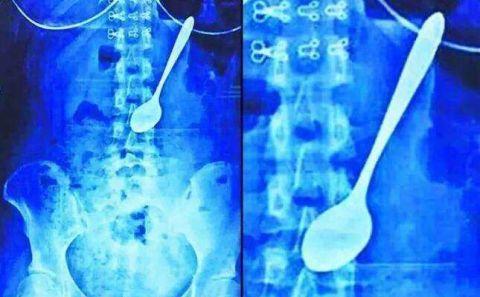

千万别把勺子放在地板上